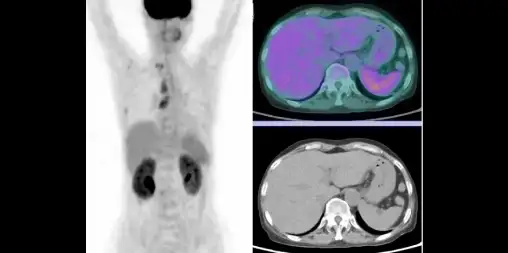

F-18 FDG

Oncology & beyond

FDG-PET uses a radioactive glucose analog to visualize metabolic activity. Primarily used in oncology (cancer imaging).